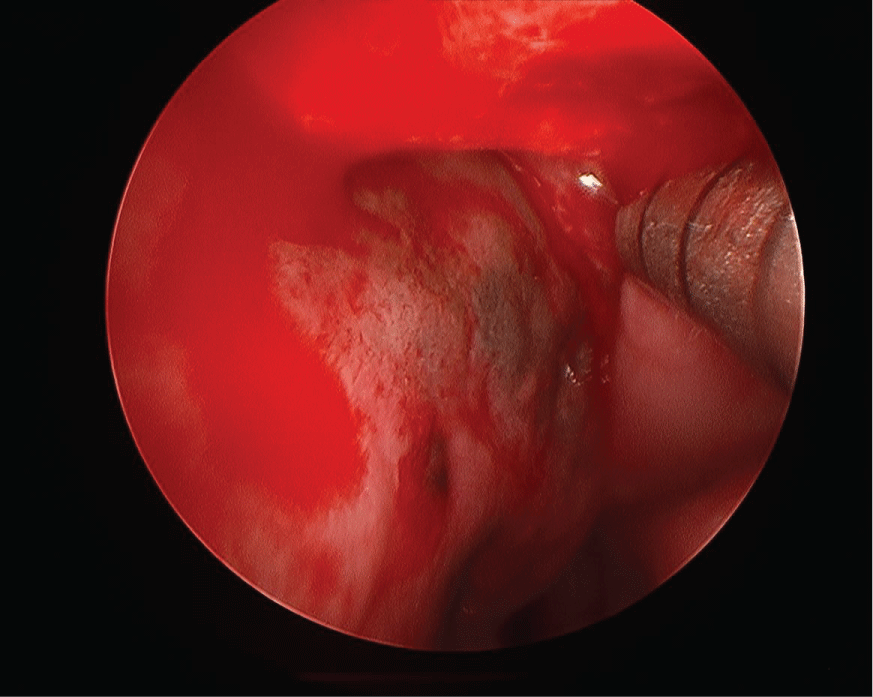

A flexible nasolaryngoscopy was performed which demonstrated a small mass extending off the posterior edge of the left septum with associated dark mucosa (Figure 1) extending beyond the mass up to the level of the superior turbinate to the left nasal floor and on the right around the choana to the right nasal floor. In addition, there was significant left nasal septal deviation. A biopsy of the nasal mass demonstrated a spindle cell melanoma. A posterior septectomy was performed including bilateral superior and right middle turbinectomy in addition to excision of the sphenoid face and bilateral nasal floor mucosa.

Figure 1: Flexible nasolaryngoscope image of pigmented area and mass at posterior edge of nasal septum. View Figure 1